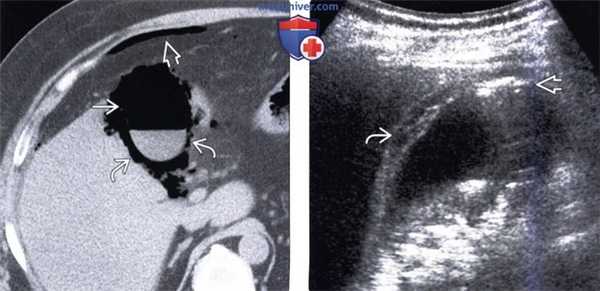

(Левый) На поперечном УЗ срезе через левую долю печени по ходу желчных протоков определяются множественные линейные эхогенные зоны, некоторые из них отбрасывают акустическую тень; такая картина отражает наличие газа в желчных протоках.

(Правый) На поперечном УЗ срезе через левую долю печени визуализируются линейные эхогенные очаги, отбрасывающие «грязную» акустическую тень; такие изменения вызваны наличием газа во внутрипеченочных желчных протоках.

3. КТ при газе в желчных протоках:

• КТ с контрастным усилением:

о Линейные/тубулярные участки газовой плотности, прилегающие к хорошо контрастируемым ветвям и крупным стволам воротной вены

- Могут выявляться в просвете желчных протоков (внутрипеченочных и/или внепеченочных) или в желчном пузыре

о Газ в желчных протоках чаще локализуется центрально, в отличие от газа в воротной вене, для которого характерна более периферическая локализация